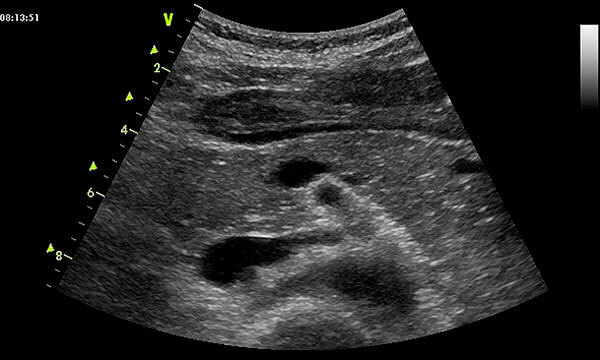

УЗИ диагностика кольцевидной поджелудочной железы: что важно знать